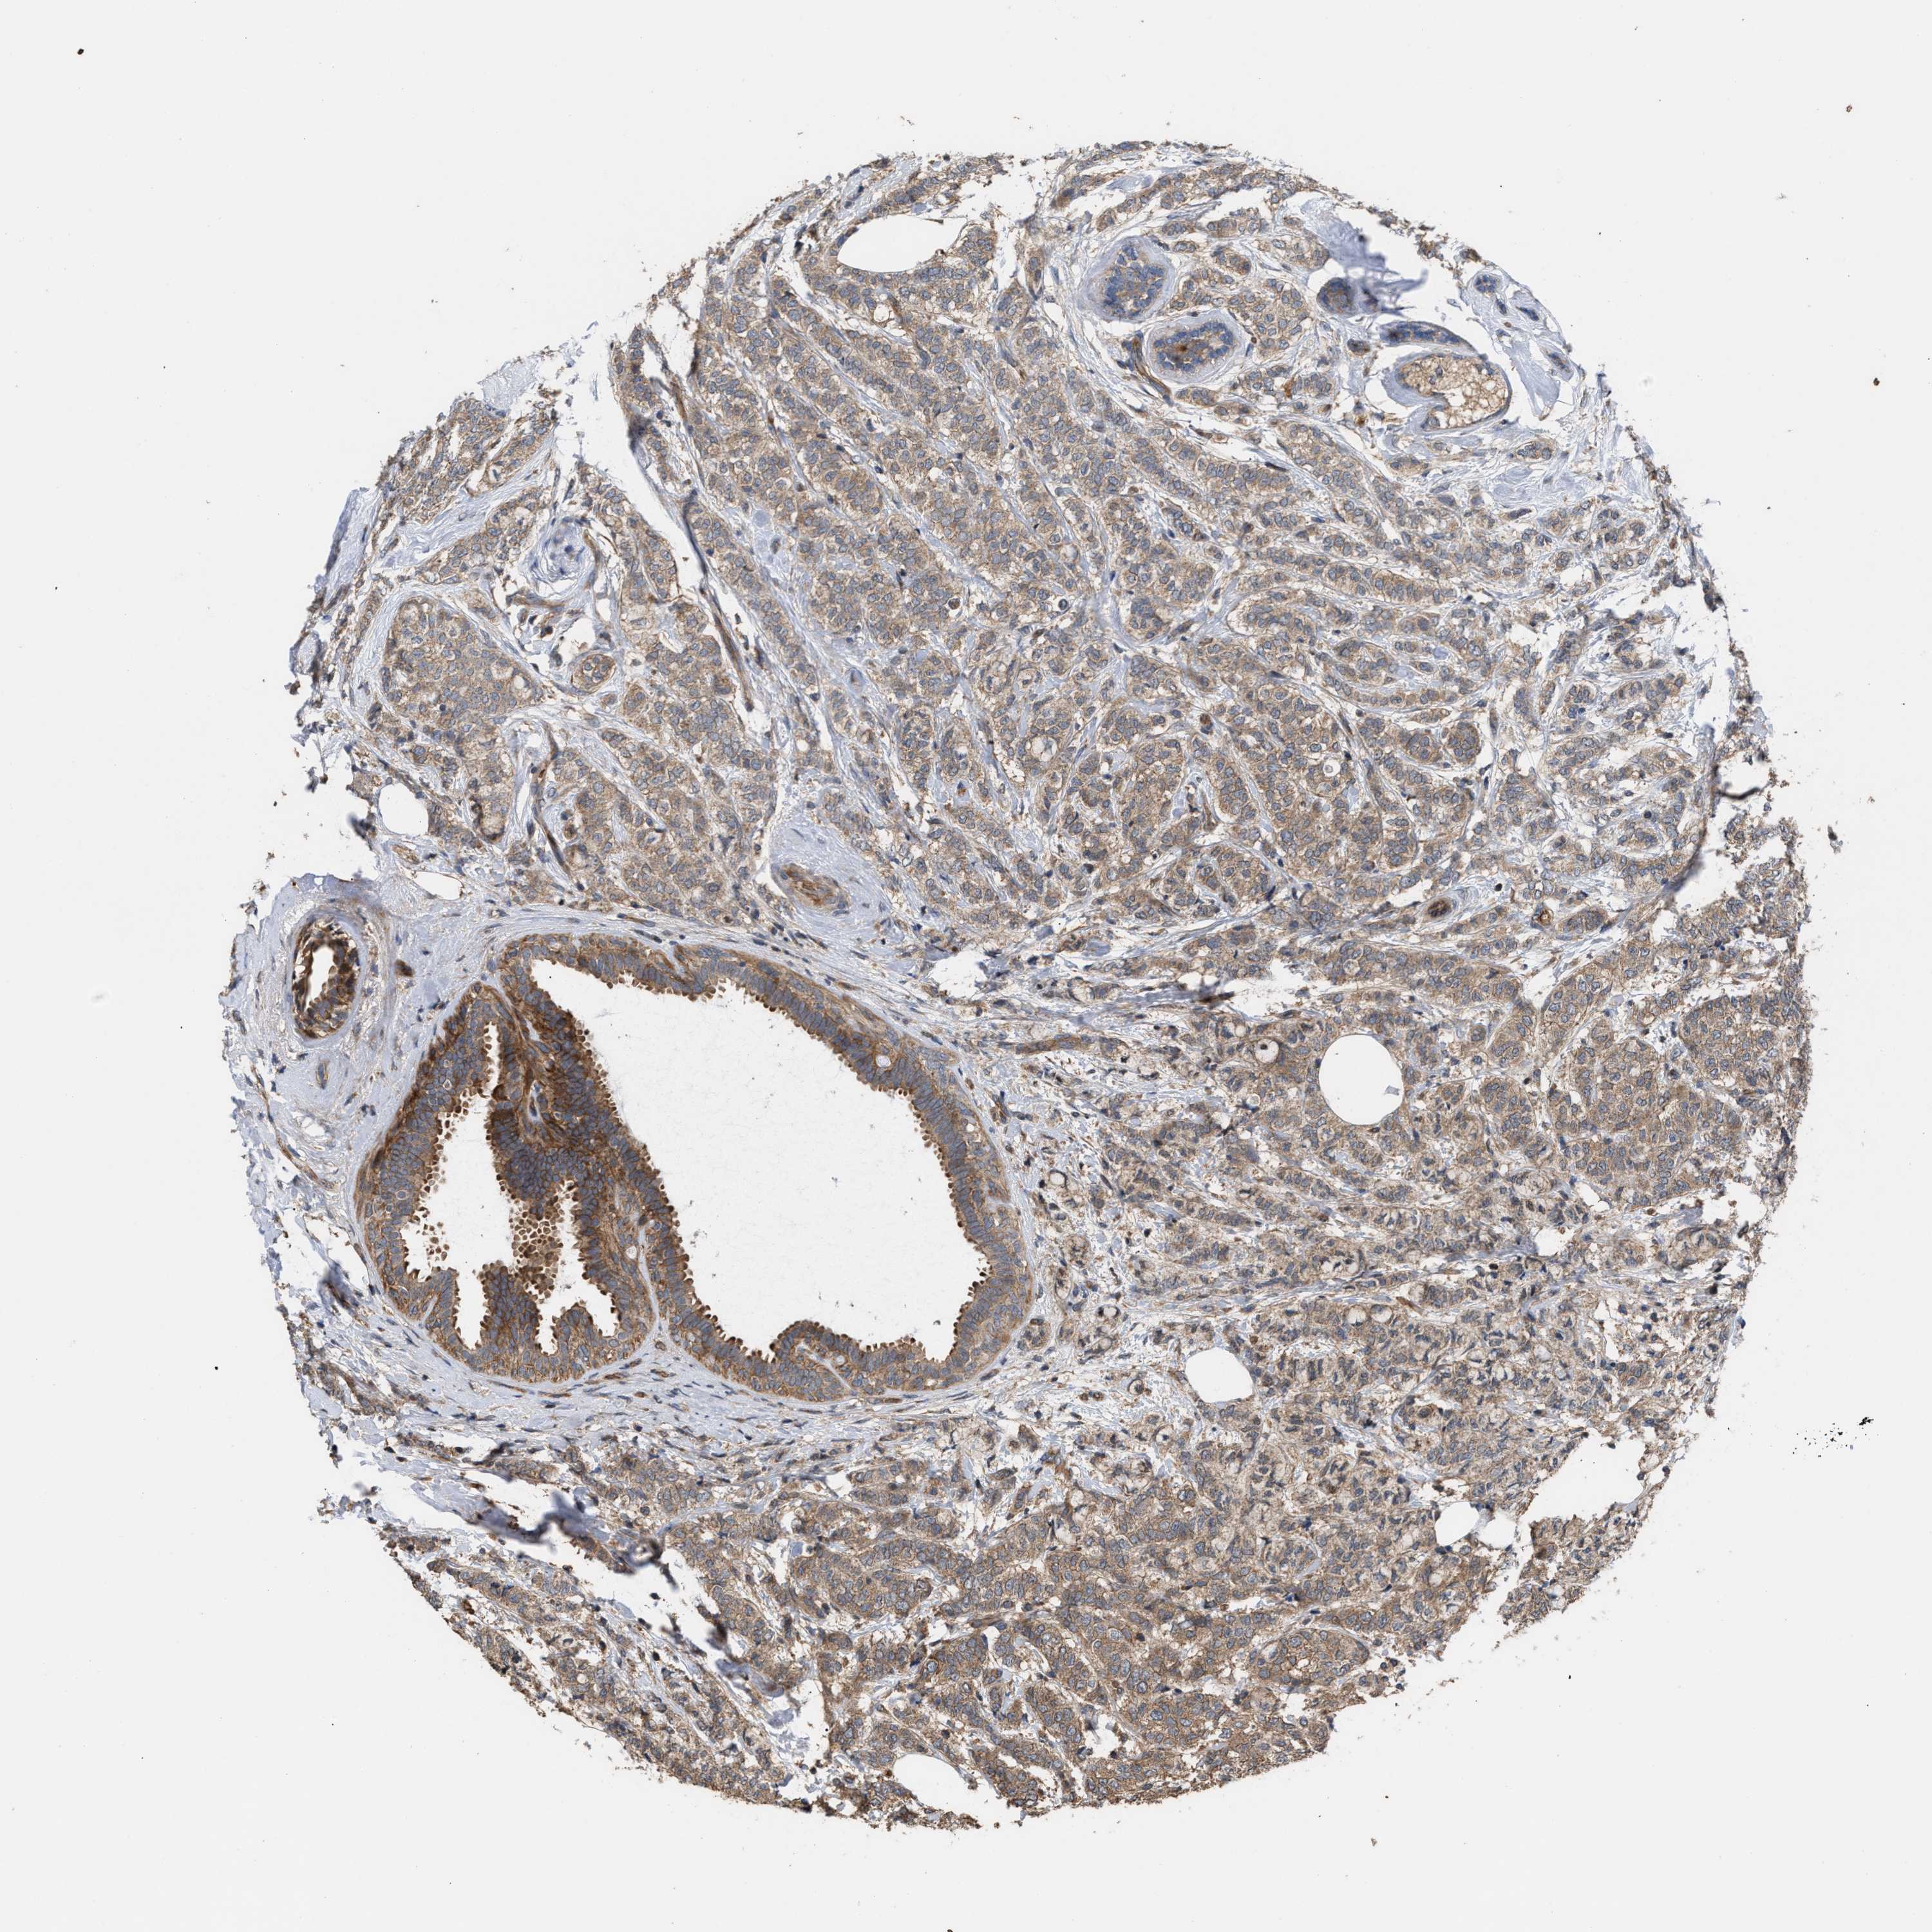

BRCA TCGA BRCA VALIDATION PROTEIN EXPRESSION

ANTIBODIES

AND

VALIDATION